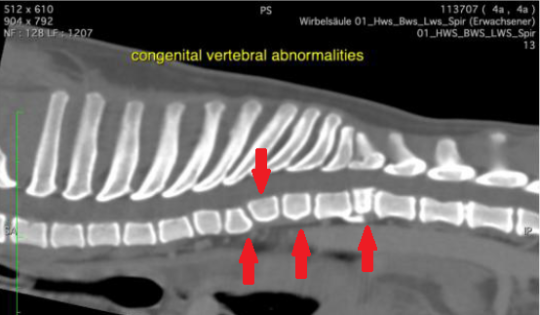

Bandscheibenvorfälle sind zwar grundsätzlich bei jedem Hund möglich, allerdings haben gewisse Rassen diesbezüglich ein stark erhöhtes Risiko. Ihnen gemeinsam ist hauptsächlich die sogenannte Chondrodystrophie - aufgrund der Züchtung von kurzen Beinen und gedrungenen Körpern leiden solche Rassentypen unter mehr oder weniger ausgeprägten Knorpel- und Knochenwachstumsstörungen, wodurch das Risiko von Bandscheibenvorfällen massiv steigt. Typische Vertreter dieses Rassetyps sind Dackel, Französische Bulldogge, Pekinese, Shi Tsu oder der Mops. Im Computertomogramm unseres Patienten ist ersichtlich, dass eine ganze Serie seiner Rückenwirbel rassebedingt missgebildet sind - statt rechteckig sind die Wirbelkörper abgerundet, keilförmig oder viel kürzer als normal (rote Pfeile). Es besteht das Risiko, dass auch hier Bandscheibenvorfälle entstehen könnten.